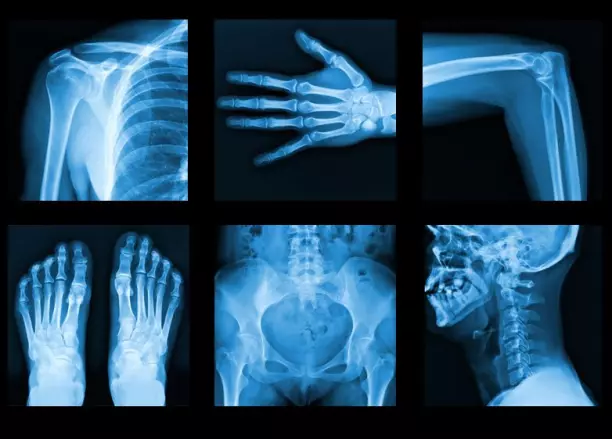

تنتمي الأشعة السينية إلى عائلة من الإشعاعات تسمى الموجات الكهرومغناطيسية. تُستخدم الأشعة السينية في المجال الطبي لقدرتها على تصوير الجسم من الداخل، خاصة العظام دون الحاجة لإجراء أي شقوق.

تساعد الأشعة السينية في تشخيص، ومتابعة، وعلاج العديد من الأمراض، وتصدر الأشعة السينية صورة ثنائية الأبعاد (2D)،تتنوع ألوانها بين الدرجات المختلفة من اللون الأبيض والأسود.

يرجع ذلك التنوع لاختلاف قوة امتصاص أجزاء الجسم المختلفة للأشعة السينية، فنجد العظام تمتص الأشعة بنسبة أكبر من غيرها نتيجة وجود الكالسيوم، فتظهر بيضاء في الصورة. أما الأنسجة الرخوة والدهون فهي تمتص كميات أقل من الأشعة فيميل لونها إلى اللون الرمادي.

يشيع استخدام الأشعة السينية في تشخيص كسور العظام، واكتشاف الإصابة بالالتهاب الرئوي، كذلك يعتمد جهاز الماموجرام المستخدم في تشخيص سرطان الثدي عبر الأشعة السينية.

تستطيع هذه الأشعة فحص معظم أجزاء الجسم، ولعل أشهر الأسباب التي قد يطلب منك الطبيب تصوير الجسم بالأشعة السينية هي: